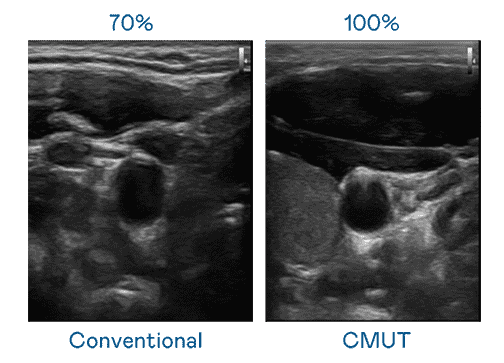

CMUT 技术是一种用电容式微机电元件来产生超音波讯号的技术。。。与传统 PZT 压电式技术相比,,CMUT 频宽增加 30%,,,更宽频的超音波讯号让影像解析度大幅提升,,,,是实现高影像品质医疗超音波扫描、、、、促进精准医疗发展的关键技术。。。。

大频宽带来超清晰影像

超音波影像的解析度高低,,,,首先取决于探头能发出的讯号频宽。。森林舞会 CMUT 可提供高清晰的超音波讯号,,,提供高频宽、、、高灵敏度、、、影像纹理细节更高的超音波影像,,,,协助医护人员缩短影像判读时间及利用精准的医疗影像进行诊断。。